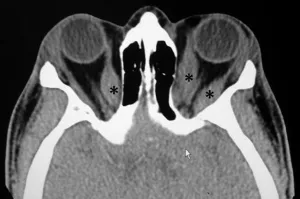

⭐ CT or MRI of the orbits typically reveals fusiform enlargement of extraocular muscle bellies with sparing of the tendons.

- Assesses Extraocular Muscles (EOMs) (📌 IMSLO: Inferior > Medial > Superior > Lateral > Obliques), optic nerve.